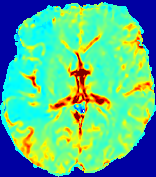

4.3.2 Diffusion Imaging via Advection-Diffusion

Slice #1Slice #2Slice #3Slice #4Slice #5Slice #6Dgtsuperscript𝐷gtD^{\text{gt}}Refer to captionRefer to captionRefer to captionRefer to captionRefer to captionRefer to captionDestsuperscript𝐷estD^{\text{est}}Refer to captionRefer to captionRefer to captionRefer to captionRefer to captionRefer to captionRefer to caption0.300.300.300.240.240.240.180.180.180.120.120.120.060.060.060.000.000.00(mm2/s)𝑚superscript𝑚2𝑠(mm^{2}/s)𝐕est𝟐subscriptnormsuperscript𝐕est2\|\bf{V}^{\text{est}}\|_{2}Refer to captionRefer to captionRefer to captionRefer to captionRefer to captionRefer to captionRefer to caption0.00300.00300.00300.00240.00240.00240.00180.00180.00180.00120.00120.00120.00060.00060.00060.00000.00000.0000(mm/s)𝑚𝑚𝑠(mm/s)

Figure 15: PIANO identifiability testing: diffusion imaging via advection-diffusion. Top row shows Dgtsuperscript𝐷gtD^{\text{gt}} used for simulating ground truth pure diffusion. Rows below show the estimated Destsuperscript𝐷estD^{\text{est}} and 𝐕est2subscriptnormsuperscript𝐕est2\|{\bf{V}}^{\text{est}}\|_{2} on corresponding slices. Note that the plotted value scale for 𝐕est2subscriptnormsuperscript𝐕est2\|{\bf{V}}^{\text{est}}\|_{2} is 0.01 of that for Dgtsuperscript𝐷gtD^{\text{gt}} and Destsuperscript𝐷estD^{\text{est}}.

Similarly, we test the behavior of PIANO when estimating both advection and diffusion from a pure diffusion-driven process. The goal is to determine if PIANO is able to recognize that there is only diffusion governing the given concentration time-series. We use the same ‘Diffusion Imaging’ data simulation of Sec. 4.2.1 as the concentration dataset, PIANO estimates both velocity 𝐕estsuperscript𝐕est{\bf{V}}^{\text{est}} and diffusivity Destsuperscript𝐷estD^{\text{est}}. Estimation results in Fig. 15 confirm PIANO’s identifiability again: the estimated 𝐕est2subscriptnormsuperscript𝐕est2\|{\bf{V}}^{\text{est}}\|_{2} is almost invisible compared to Destsuperscript𝐷estD^{\text{est}}, even plotted with a 1%percent11\% value range compared to that for Destsuperscript𝐷estD^{\text{est}}. On the other hand, Destsuperscript𝐷estD^{\text{est}} achieves comparable estimation performance as ‘Diffusion Imaging via Diffusion’ in which PIANO predicts Destsuperscript𝐷estD^{\text{est}} alone (shown in Fig. 13).